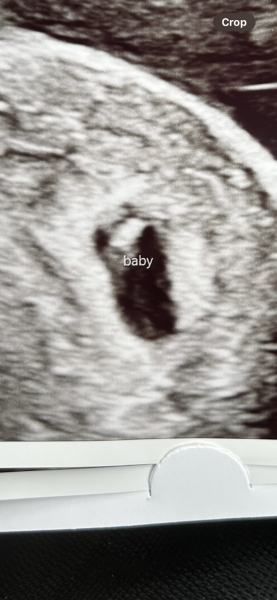

Thank you! Just had it now. All good and one strong heartbeat 😀

Congratulations! Such a cute little blob!

@Lemonbalm8 I don't know if she measured the heartbeat but she said it was fast and strong. She measured me at 6+6. Fingers crossed for yours 😀